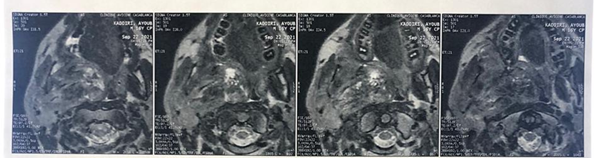

The patient then underwent MRI of the face, which

revealed a voluminous, largely necrotic tissue lesion in the right

infra-temporal fossa, measuring 94 mm in long axis, with irregular contours in

T1 hyposignal, discrete T2 hyper signal, diffusion hypersignal with low ADC,

intensely and heterogeneously enhancing after injection of gadolinium,

delineating areas of necrosis.

Superiorly and medially, it infiltrates the right parapharyngeal space

and the nasopharynx, partially filling its lumen. Superiorly and laterally, it

compresses the homolateral parotid gland and reaching the subcutaneous soft

tissue (Figure 3).

Figure 3: MRI on axial section

showing the tumor that infiltrates the right parotid, the right parapharyngeal

space and the nasopharynx, partially filling its lumen